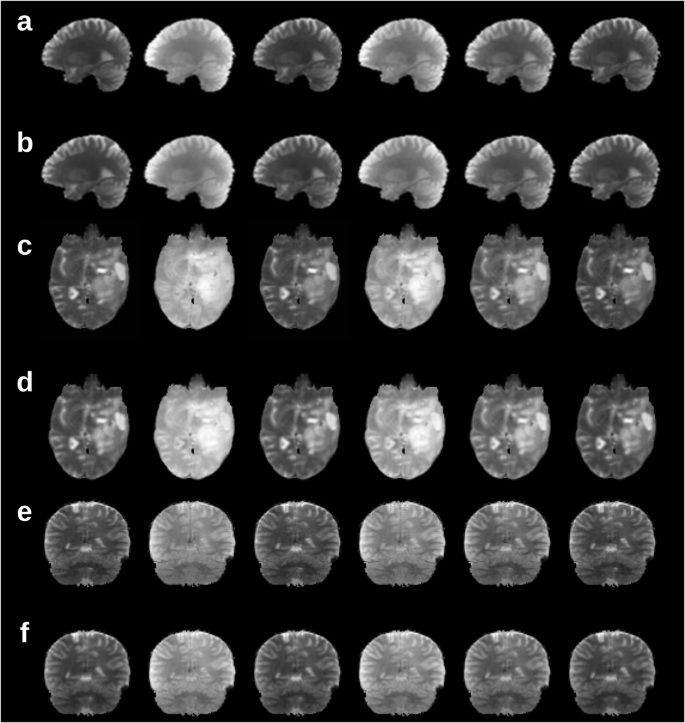

A comparison between representative ground truth (a, c, e) and TBMF-predicted (b, d, f) molecular MRI contrast-weighted images in the human brain. a, b Semisolid magnetization transfer (MT)-weighted images from an unseen subject. c, d Amide proton transfer chemical exchange saturation transfer (CEST)-weighted images from a brain tumor patient scanned at an unseen imaging site. e, f Semisolid MT-weighted images from an unseen subject scanned at an unseen imaging site with different hardware to that used for training.

Biophysical-model-free multi-contrast prediction

The core module was validated for generating on-demand molecular (semisolid magnetization transfer (MT) and amide proton chemical exchange saturation transfer (CEST)-weighted) images. The full reference imaging protocol consisted of 30 pseudo-random RF excitations (Supplementary Fig. 1)27. The first six images were used for per-subject calibration, followed by TBMF predictions of the multi-contrast images associated with the next six response images (Fig. 1a). A representative example of the TBMF output compared to the ground truth for each of the validation datasets is shown in Fig. 2 and whole-brain 3D reconstruction output is provided as Supplementary Movie 1 (semisolid MT) and Supplementary Movie 2 (amide). A visual, perceptive, and quantitative pixelwise similarity was obtained between TBMF output and ground truth. This is reflected by a structural similarity index measure (SSIM) > 0.96, peak signal-to-noise ratio (PSNR) > 36, and normalized mean-square error (NRMSE) < 3% (Table 1).